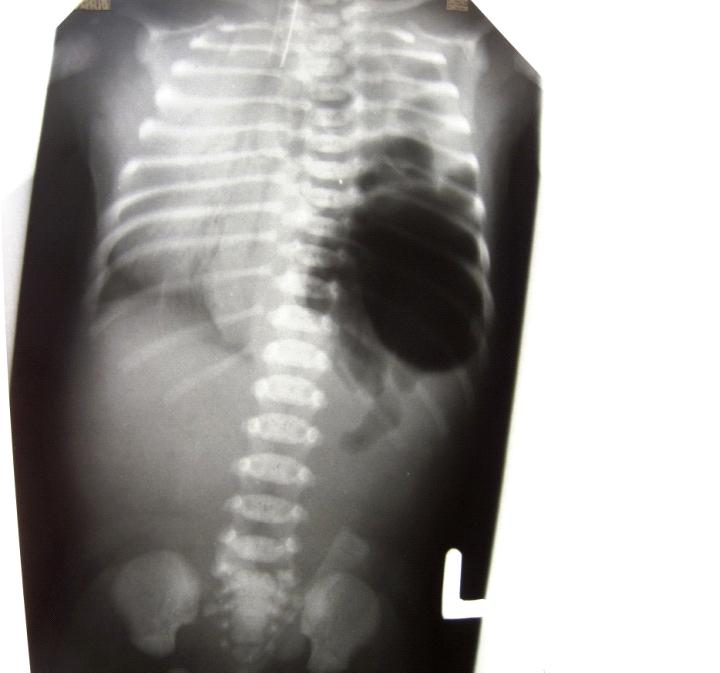

Noworodek płci żeńskiej, urodzony o czasie z Apgar 8, przekazany do oddziału intensywnej terapii noworodka w 2. dobie życia w ciężkim stanie ogólnym, zaintubowany z rozpoznaniem postępującej niewydolności oddechow -krążeniowej i podejrzeniem odmy opłucnowej lewostronnej. Wykonano zdjęcie RTG klatki piersiowej. Uwzględniając opisany gwałtowny przebieg kliniczny i

przedstawione RTG wymień najbardziej prawdopodobną przyczynę stanu dziecka: